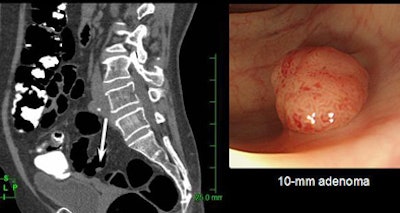

| Minimal-prep VC detected a 10-mm adenoma in the sigmoid colon (left); fecal tagging can be seen in the bright regions of the colonic lumen; colonoscopic confirmation is at right. All images courtesy of Janne Näppi, Ph.D., and Koichi Nagata, Ph.D. |